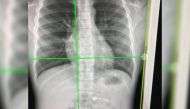

Apple Airpod as X'mas gift lands up in 7-yr-old's stomach 04 Jan 2020 - 12:02 pm

X-rays shows the wireless headphone inside the body.